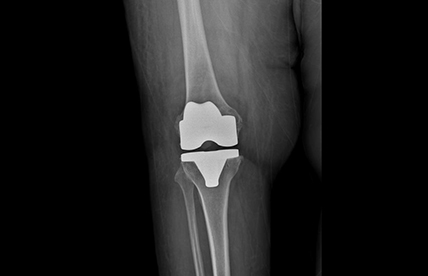

Diz Kireçlenmesi

Gonartroz, diz ekleminde kıkırdak dokunun zamanla aşınmasıyla ortaya çıkan bir hastalıktır. Kıkırdak yüzeyin bozulması sonucu kemikler birbirine daha fazla temas eder ve bu durum ağrı, sertlik ve hareket kısıtlılığına yol açar. Özellikle merdiven çıkarken, uzun süre ayakta kalındığında veya çömelme sırasında ağrı artabilir. İleri evrelerde dizde şişlik ve şekil bozukluğu da görülebilir.

Tedavide amaç ağrıyı azaltmak ve eklem fonksiyonunu korumaktır. Erken dönemde kilo kontrolü, egzersiz, fizik tedavi ve ağrı kesici ilaçlar önerilir. Diz çevresi kaslarının güçlendirilmesi şikayetleri azaltmada önemlidir. Gerektiğinde eklem içine enjeksiyonlar uygulanabilir. İleri evre gonartrozda ise diz protezi ameliyatı oldukça başarılı ve yüz güldürücü bir tedavi seçeneğidir. Uygun hastalarda ağrıyı büyük ölçüde ortadan kaldırır ve hastaların günlük yaşam aktivitelerine geri dönmesini sağlar. Tedavi planı hastanın yaşı, şikayetleri ve hastalığın evresine göre belirlenir.